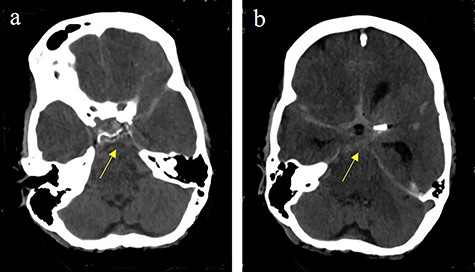

Subarachnoidal bleeding into the basal cistern-axial cranial computed tomography (cCT) at the level of (a) prepontine cistern (arrow) and (b) pentagonal cistern.

On the next day (Day 9 post-op), the patient suffered from acute and devastating headaches, with screaming and enuresis. An emergency computed tomography (CT) was carried out and displayed a prepontine and retroclival subarachnoid hemorrhage (Hunt & Hess Grade I), (Fig. 2). For further evaluation, a digital subtraction angiography (DSA) was conducted, and it showed a pseudoaneurysm of ophthalmic1/supraclinoid2/C23 part of the left ICA, which was directly treated by a flow diverter (Derivo®—4,5/20), with remaining rest flow (Fig. 3). The patient was transferred to the ICU, transcranial doppler sonography was performed and revealed normal flow. In the following course, the patient suffered from Terson’s syndrome and hyponatremia due to SIADH, but after clinical improvement, was transferred back to normal station after 10 days of post-operative monitoring. Furthermore, the patient was plagued with cephalgia and nausea, which could not be compensated with analgetics and antiemetics. On the 20th post-operative day after the epileptic seizure with postictal vigilance reduction, an emergency CTA was conducted showing progressive SAH (Fig. 4) and a growing pseudoaneurysm as well as generalized vasospasm with posthemorrhagic hydrocephalus. For an emergency CSF diversion, an external ventricle drain was placed. The repeated DSA showed a growing false aneurysm which was treated with two additional flow diverters (2× Derivo®—4,5/20) as well as coiling (HydroSoft™ 2/3 and 2× 1,5/2) by endoleak (Fig. 5). The vasospasms were treated by an intraarterial spasmolysis (Fig. 6).